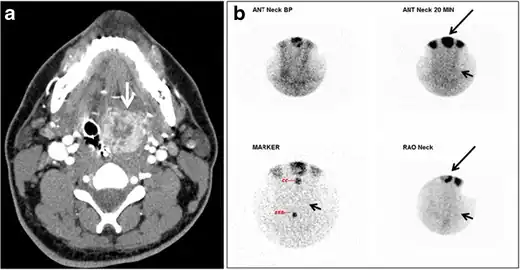

| CT scan and scintigraphy images of lingular ectopic thyroid | |